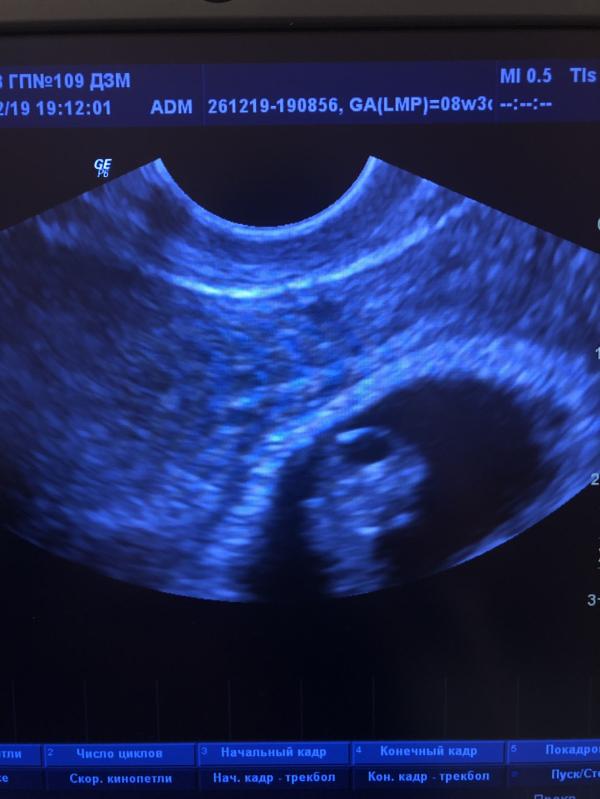

Сегодня ходила на УЗИ, срок 8нед 1день, показали как бьется сердце), сильно вырос с прошлого УЗИ ( делали 3 недели назад). С ХЧГ не пойму, но вроде хорошо. Остаётся только ждать... ещё долгих 7 месяцев. Чем заниматься? Что полезное сделать для себя и малыша?